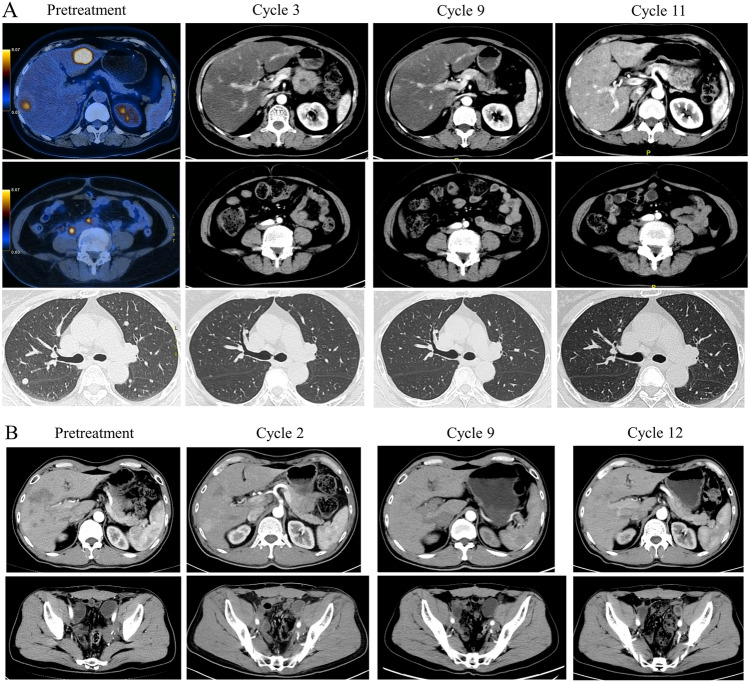

The median PFS was 5.4 months, and the median OS was not reached. The 6-month and 1-year PFS rates were 38.8% and 15.5%, respectively (Fig. 1A). The 1-year OS rate was 79.6% (Fig. 1B). The median PFS for patients who received RC48 combined with immunotherapy and those treated with RC48 alone was 8.5 and 5.4 months, respectively (HR = 1.15, 95% CI 0.46–2.88, P = 0.75) (Fig. 1C). The median PFS for patients with HER2 2 +/3 + expression and those with HER2 1 +/0 expression was 5.9 and 3.0 months, respectively (P = 0.11, HR = 0.34, 95% CI 0.09–1.28) (Fig. 1D). The PFS in patients received RC48 as first line was 6.6 months, compared with 4.2 months in those with second- and later-line treatment (P = 0.09) (Figure S1). The swimmer plot for all patients is shown in Fig. 2. For the 25 patients who achieved SD or PR, the DOR was 4.0 months. Patient #6 showed the best tumor response of PR (Fig. 3A) and a DOR of 9.1 months, but she discontinued RC48 due to grade 2 hypoesthesia. Patient #10 relapsed 11 months after adjuvant cisplatin and gemcitabine and rapidly progressed after combination of EV and pembrolizumab. Then, he was treated with RC 48 monotherapy and achieved good PR with a DOR of 7.6 months (Fig. 3B).

Fig. 3.

Representative pre-treatment and post-treatment images in patients #6 (A) and #10 (B)